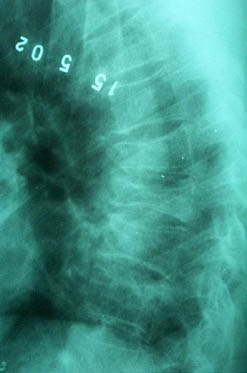

Компрессионный перелом

В декабре 99 года перенес геморрагический а потом и ишемический инсульт левой задне-лобно-височной области. Выписался со значителсным улучшением неврологической симптоматики. Через год, на фоне обычного самочувствия, пожаловался на боль в спине, после чего появилось тоническое напряжение правой руки, половины туловища, перерастающее в приступ с судорогами по типу тонико-клонических и потерей сознания. Госпитализирован. На CТ выявлен большой очаг в виде кистозной полости. Компрессионный перелом 8-9 грудных позвонков. В последующем, на протяжении полутора лет в общей сложности отмечено 5 аналогичных по формуле припадков. Падения с высоты во время приступов небыло. Также отрицает травмы позвоночника в анамнезе. Повторная R-графия и СТ позвоночника выявила патологический компрессионный перелом и остеопороз тел Th 6; 7; 8; 9, (отрицательная динамика). Наличие необластомного процесса не выявлено. Все анализы, включая паратгормон, в пределах нормы кроме: Са-Т - 2.66 (от 2.02 до 2.60) Р - 1.72 (от 081 до 1.62) СОЭ - 34мм/час Снимки 1, 2, 3, 4 прилагаются. Возникает ряд вопросиов: Может ли деструкция в левой задне-лобно-височной области быть связана с системним остеопорозм позвонков и пат. переломом? Моигут ли эпилптические приступы явиться причиной компрессионного перелома позвонков? Какие дополнительные исследования нужны для дифдиагностики болезни Куммелля? Тактика лечения (корсет?), показания и противопоказания к хирургическому вмешательству на позвонках в данной ситуации Прогноз? Буду благодарен любым соображениям, Аршак Мирзоян